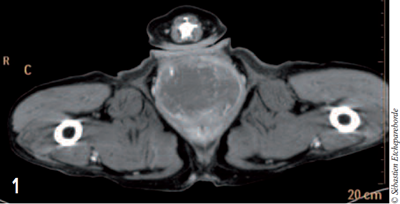

photo 3

Photo 3 – Coupe transversale de la masse où l’on aperçoit le colon comprimé dorsalement. La masse mesurait 10 cm de long.

Une sonde urinaire avait été mise en place préalablement pour repérer l’urètre au scanner. La masse mesurait 10 cm de long sur un diamètre d’environ 5 cm. Aucune des structures environnantes ne semblaient envahies par la masse.